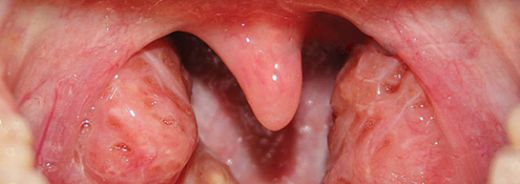

Sol Bademcik Şişmesi: Belirtileri ve Tedavisi

Sol bademcik şişmesi, genellikle boğazın arka kısmında yer alan lenfoid dokunun iltihaplanması veya enfekte olması durumudur. Bademcikler, bağışıklık sisteminin bir parçası olarak, vücut savunmasında önemli bir rol oynamaktadır. Bu durum, çeşitli etkenlerden kaynaklanabilir ve genellikle enfeksiyon belirtisi olarak ortaya çıkar.

Sol bademcik şişmesi, çeşitli belirtilerle kendini gösterebilir. Bu belirtiler şunları içerebilir: - Ağrı veya rahatsızlık hissi: Şişen bademcik, yutkunma sırasında ağrıya neden olabilir.

- Yutma zorluğu: Bademciklerin büyümesi, yiyeceklerin yutulmasını zorlaştırabilir.

- Boğazda tahriş: Şişmiş bademcikler, boğazda gıcırtı veya kaşıntı hissi yaratabilir.

- Ses değişikliği: Bademciklerin şişmesi, ses tellerine baskı yaparak sesin değişmesine neden olabilir.

Sol bademcik şişmesi yaşadım ve gerçekten rahatsız edici bir durum. Boğazımda ağrı ve yutkunma güçlüğü ile birlikte beyaz lekeler oluştu. Tedavi için doktora başvurdum. Tek taraflı bademcik şişmesi doktor sitesinde de belirttiği gibi önemli bir durum, dikkat edilmesi lazım.

Alpartur, yaşadığın bu durum gerçekten de rahatsız edici olabilir. Boğazdaki ağrı ve yutkunma güçlüğü, günlük yaşamı olumsuz etkileyebilir. Beyaz lekelerin varlığı, enfeksiyon belirtilerine işaret edebilir ve bu nedenle doktora başvurman çok önemli bir adım.

Dikkat Edilmesi Gerekenler

Tek taraflı bademcik şişmesi, bazen daha ciddi durumların bir belirtisi olabileceğinden, doktorun önerilerini dikkatle takip etmekte fayda var. Özellikle ateş, şiddetli ağrı veya nefes alma zorluğu gibi belirtiler varsa, derhal sağlık kuruluşuna başvurmak gerekebilir.